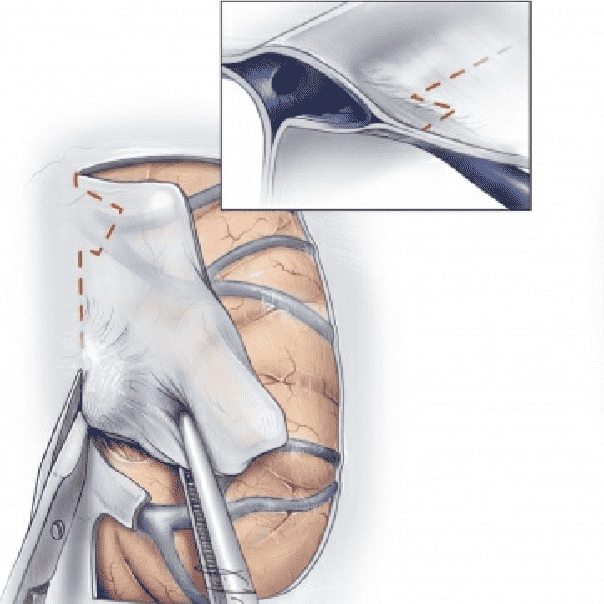

■ 围绕肿瘤及强化硬膜四周切开硬膜,翻向矢状窦侧,进一步切断肿瘤硬膜血供

■ 切开中线侧硬膜时,注意避开硬膜窦,如不慎切开,予以缝合止血

■ 人工硬膜修补,运用缝合硬膜水密修补